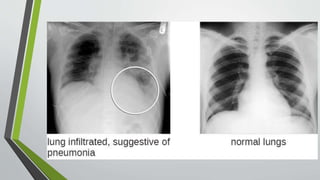

• Chest x-ray: Identifies

structural distribution (e.g.,

lobar, bronchial); may also

reveal multiple

abscesses/infiltrates,

empyema(staphylococcus);

scattered or localized

infiltration (bacterial); or

diffuse/extensive nodular

infiltrates (more often viral).

In mycoplasmal pneumonia,

chest x-ray may be clear.

. • Chest x-ray:Identifies structural distribution (e.g., lobar, bronchial); may also reveal multiple abscesses/infiltrates, empyema(staphylococcus); scattered or localized infiltration (bacterial); or diffuse/extensive nodular infiltrates (more often viral). In mycoplasmal pneumonia, chest x-ray may be clear.